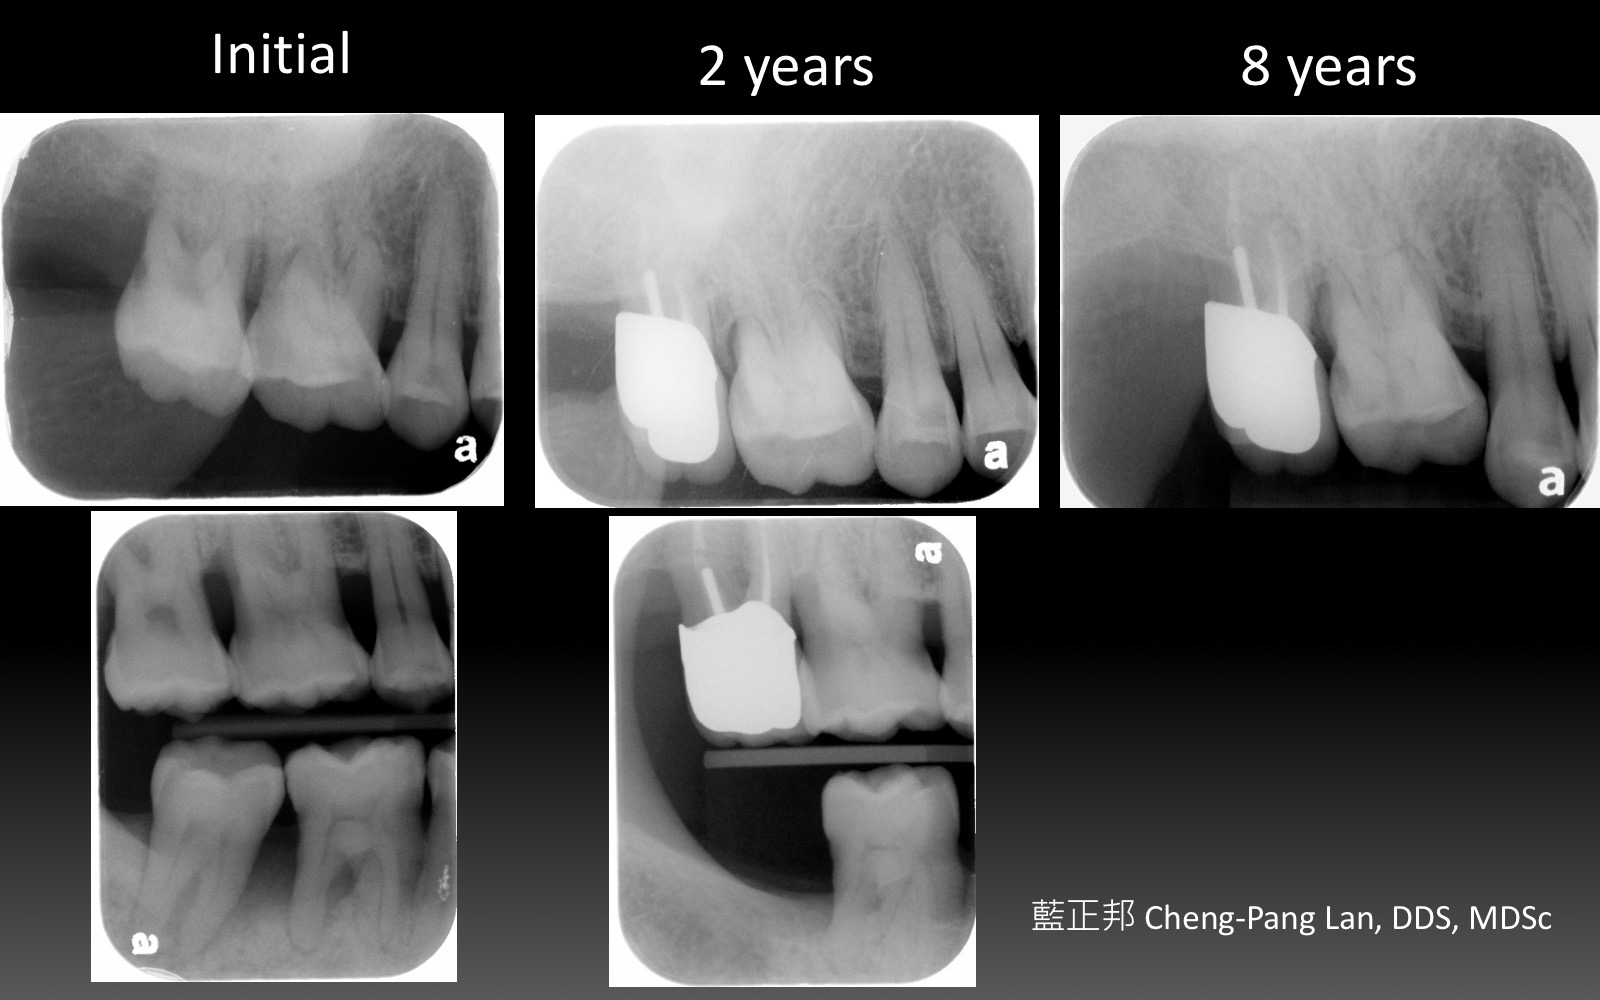

老師常常暗示著大家,implant與natural teeth之間,留下natural teeth比較好。這個我真的相信,在牙周病科的每一位學弟妹也都相信,甚至我相信週六在場的牙周病醫師都認同,但是大家有沒有想過,每隔週三一起開會的Prosthodontist、 Orthodontist都相信嗎?甚至,從實習醫師畢業就進入職場服務病人的學弟妹們,都相信嗎?